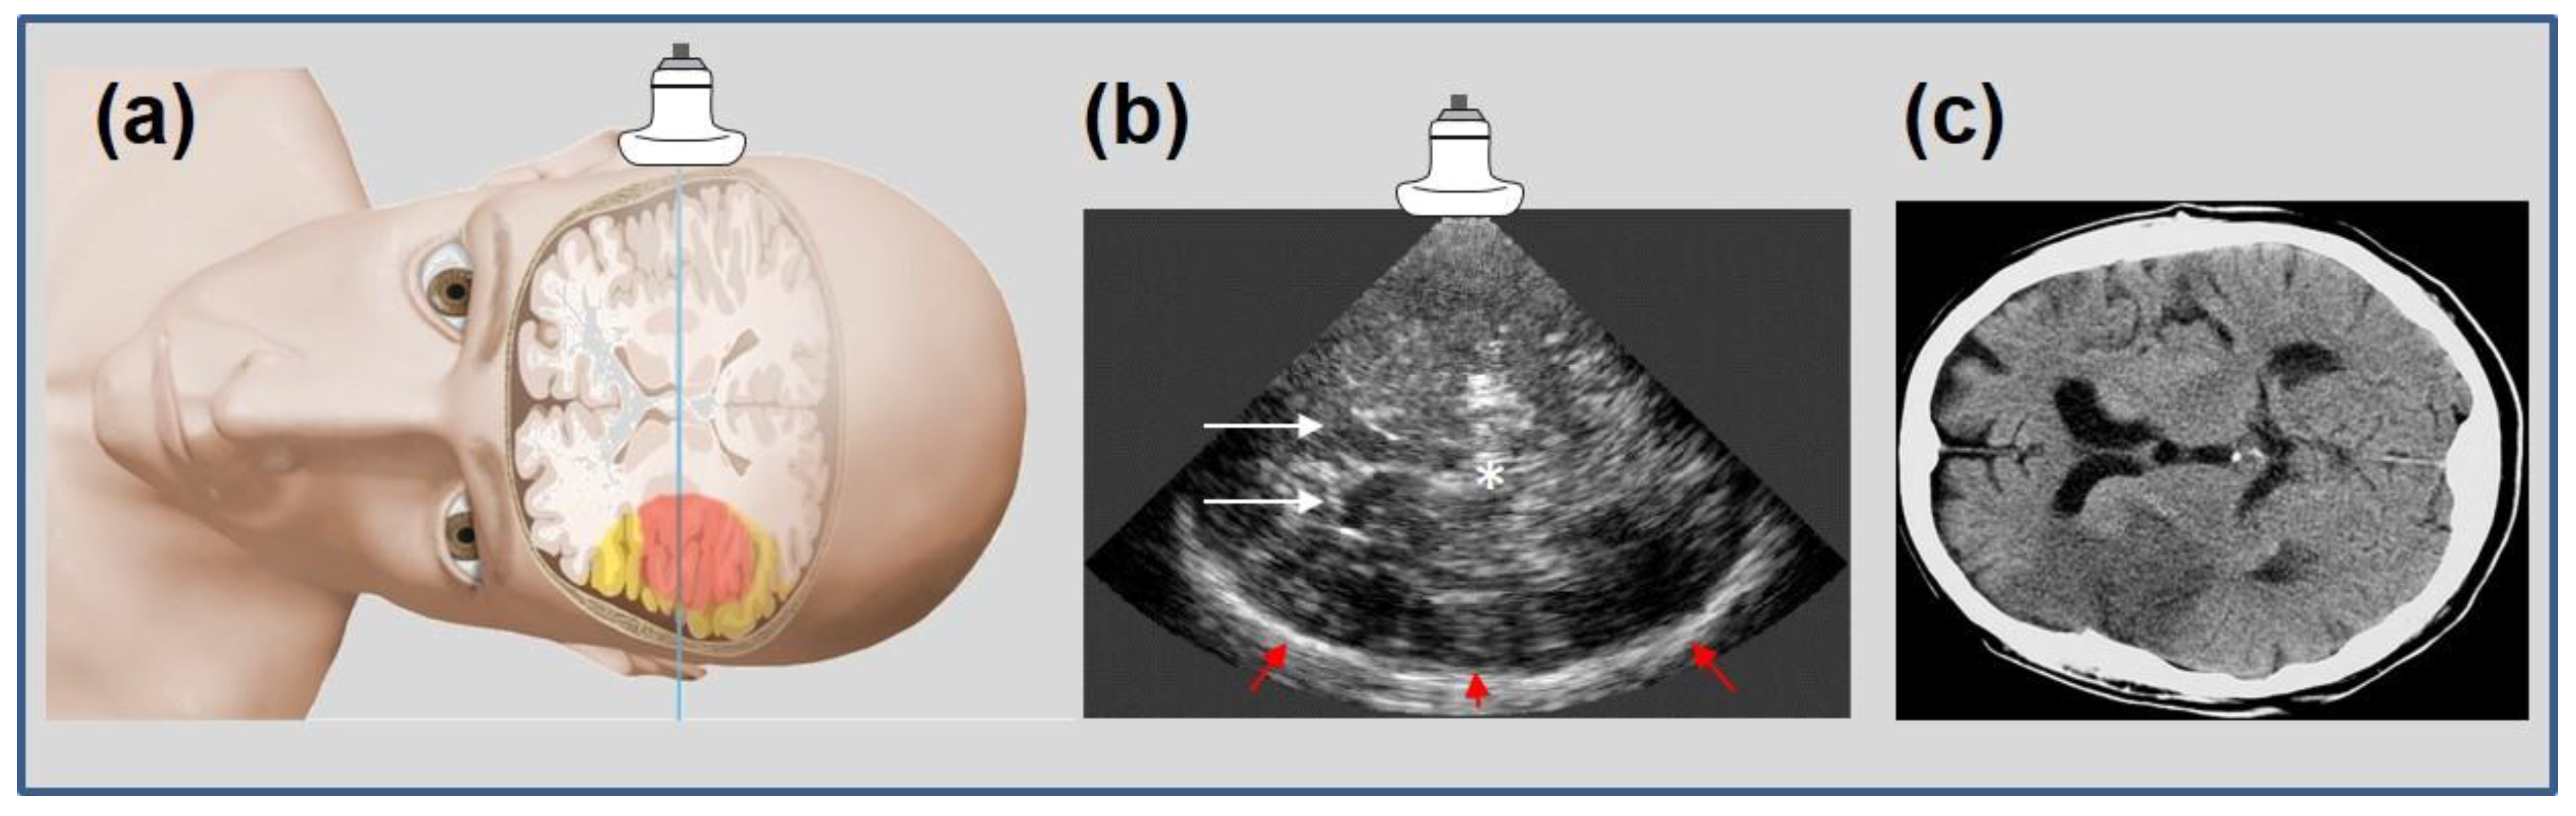

- Kern, R.; Kablau, M.; Sallustio, F.; Fatar, M.; Stroick, M.; Hennerici, M.G.; Meairs, S. Improved detection of intracerebral hemorrhage with transcranial ultrasound perfusion imaging. Cerebrovasc. Dis. 2008, 26, 277–283. [Google Scholar] [CrossRef]